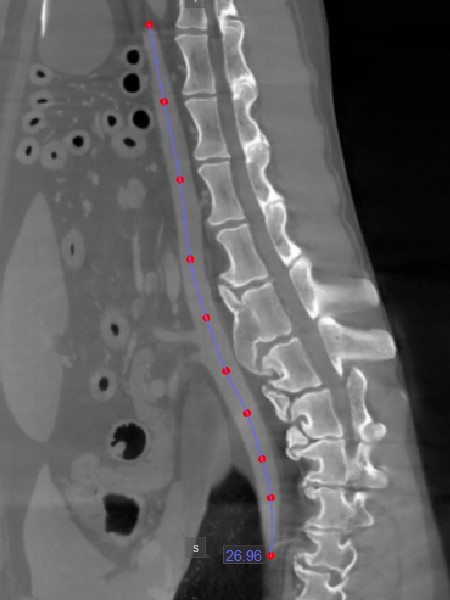

Pfadlänge¶

Das Werkzeug Pfadlänge ermöglicht es Benutzern, die Länge unregelmäßiger Linien oder die Kontur komplexer Formen entlang eines nichtlinearen Pfads zu messen.

Wählen Sie das Werkzeug Pfadlänge aus und weisen Sie es einer der verfügbaren Maustasten zu. Starten Sie die Messung, indem Sie Punkte entlang eines nichtlinearen Pfads auf der aktiven Bildschicht setzen. Während der Benutzer die Punkte setzt, verbindet die Software sie automatisch und erstellt den Pfad.

Schließen Sie die Messung ab, indem Sie beim Setzen des letzten Punkts des Pfads doppelklicken oder die rechte Maustaste verwenden, um den Pfad sofort zu berechnen. Die Länge des Pfads wird zusammen mit der Messung angezeigt.

Ändern Sie den Pfad, indem Sie einen der Punkte, die ihn beschreiben, mit dem Werkzeug Standard verschieben.